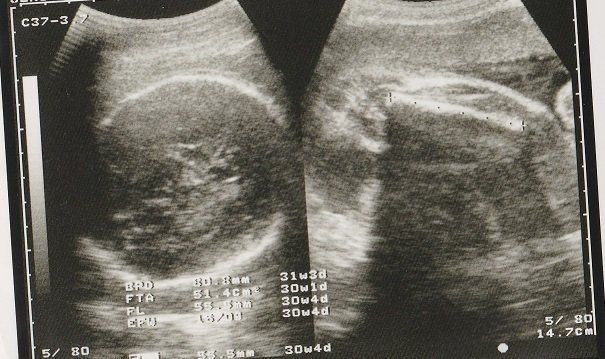

妊娠30週目のエコー写真 お母さんも大きくなる時期

赤ちゃんも順調に育っていますが、お母さんの体重も増え気味に…。「あまり体重が増えると管理入院ですよ」と、看護婦さんに釘を刺されました。

妊娠32週目のエコー写真 おなかもぱんぱんです。

AC(おなかの周囲の長さ)などから、赤ちゃんの推定体重を計算するようです。赤ちゃんのおなかも大きくなっていますが、お母さんのおなかもぱんぱんです。